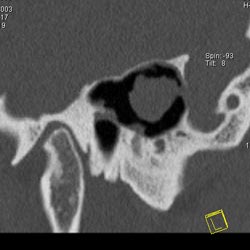

Рис. 10. Принципы КТ высокого разрешения (КТВР) на примере исследования

пирамиды височной кости. Применены тонкие срезы (0.5 мм) и "острый" алгоритм

реконструкции (кернель 90). (Слева) отчетливо видны элементы внутреннего

уха - улитка, полукружные канальцы. (В центре) показана проекция продольного

сечения височно-нижнечелюстного сустава. (Справа) - холестеатома.